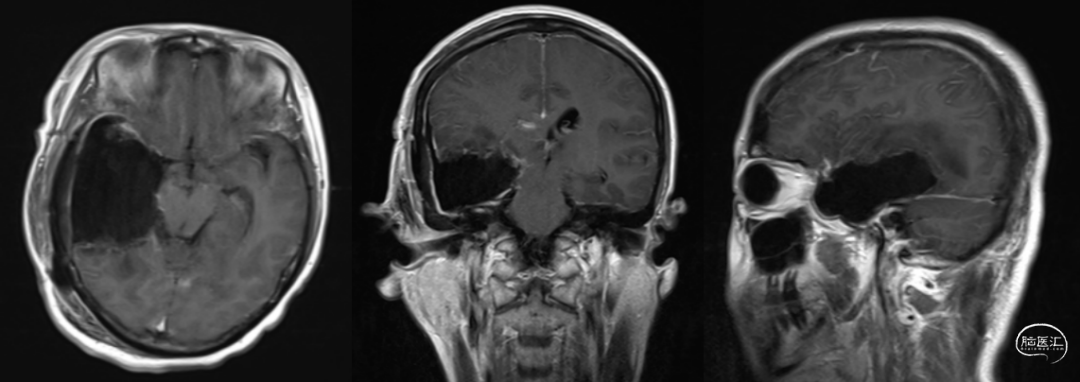

图2. 术前MRI提示右侧颞叶深部占位,高级别胶质瘤可能。

图3. 术后第1天MRI提示右侧颞叶肿瘤切除术后改变,肿瘤切除范围满意。